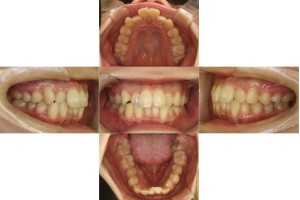

当院の症例

半年経過の口腔内の状態です。

上顎左右ともに4番目、下顎右の1番目を抜歯し、裏側矯正(リンガル)で歯を動かしていきます。